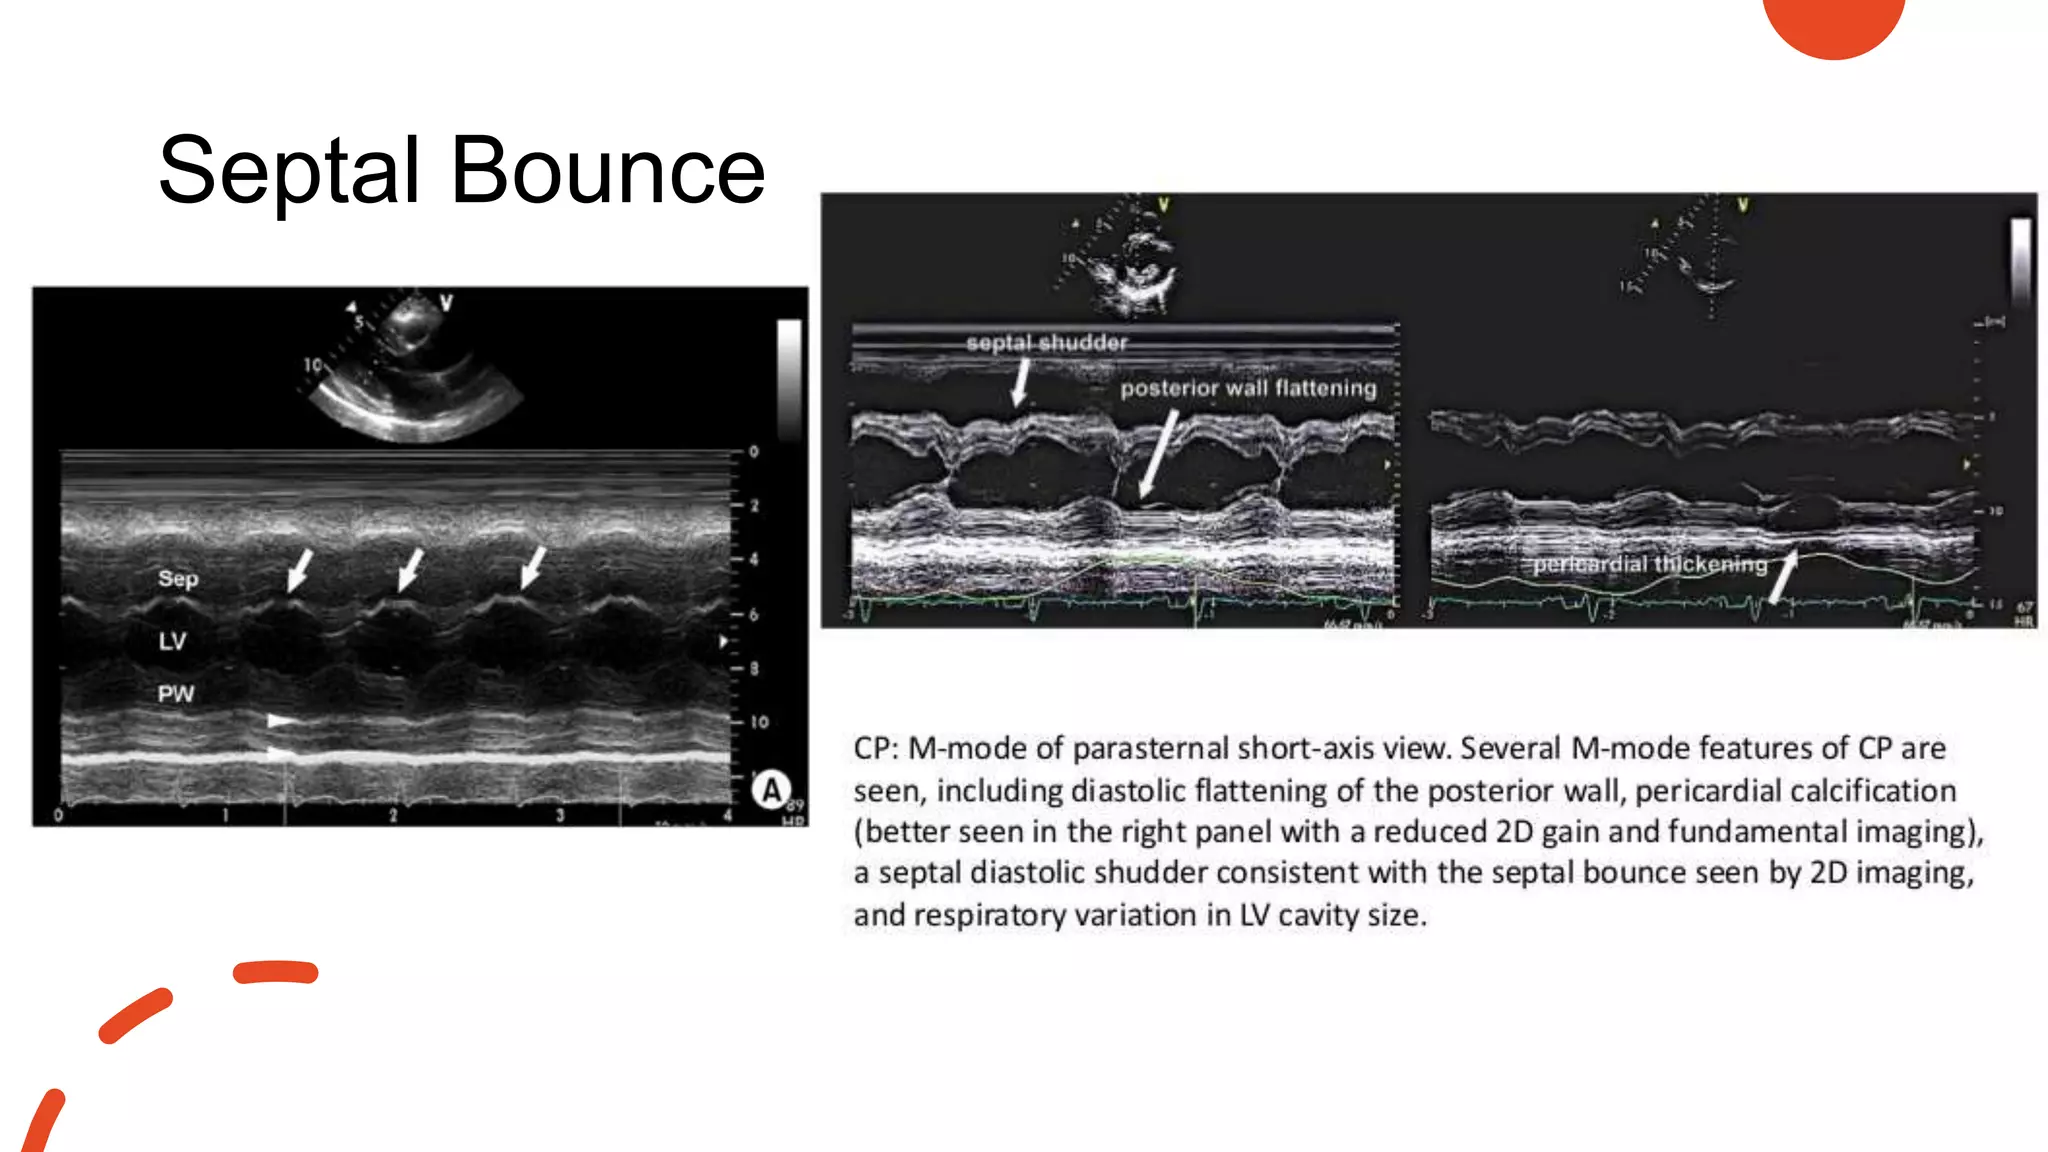

Constrictive

pericarditis

• Pericardial thickening

• Paradoxical septal motion

• Septal bounce ( abrupt displacement of the

IVS during early diastole)

• Flattening of mid & late diastolic motion of the

posterior LV wall

• Rapid early diastolic, or E-F slope of the mitral

valve

• Rapid downward motion of the posterior aortic

wall in early diastole

• Premature opening of pulmonary valve

• Dilated IVC with blunted respiratory changes

Septal bounce

• sign of ventricular interdependence

• ventricles are constricted (tethered by the pericardium)  motion of the ventricular

walls is markedly reduced and the volume of the heart is fixed

• Changes in ventricular volumes and pressures are then reflected through

deviations of the septum

• #108 M-mode echocardiography shows the characteristic findings of septal bouncing ("double components"; arrow) with an increased pericardial thickness (arrowhead)